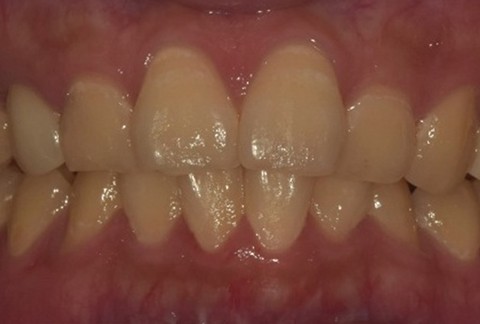

임플란트-전후사진